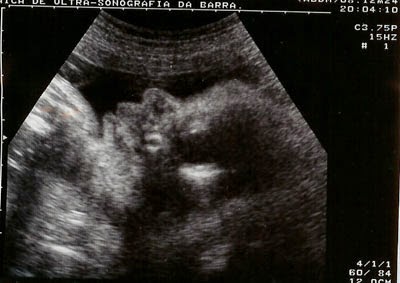

Duvida da leitora: Quantos ultrassons sao feitos durante a gestação

Ela queria saber qtos ultrassons devem ser feitos durante a gravidez...eu demorei um pouco...mas estou postando hj pra tirar sua duvida,rsrs,,,viu Su.

Ultrassom na Gravidez

As ondas sonoras que o aparelho de ultrassom emite e essas se chocam com a parte sólida do que encontra pela frente, assim forma imagens. Esse exame é inofensivo para mamãe e bebê então não se preocupe se precisar fazer mais algum ultrassom na gravidez, mais que quantidade indicada a baixo.

O ultrassom normalmente é aconselhado no principio da gravidez por duas razões, para saber se a gravidez está no lugar certo de quanto tempo é a gestação e a quantidade de fetos. Após o período inicial, o ultrassom é feito para acompanhar o desenvolvimento do feto, saúde da placenta e saber se está tudo conforme deveria naquela idade gestacional. É importante saber, que o tempo é necessário para o primeiro ultrassom. Se feita antes da hora, pode não detectar a gravidez e então provocar preocupação desnecessária na gestante.

No pré-natal feito pela unidade publica de saúde tem como meta 3 ultrassonografias durante a gravidez, 1 a cada trimestre. Essa quantidade é considerada ideal para detectar algum problema e saber se o bebê está adequado pra aquele tempo gestacional. Porém quem tem convênio, plano de saúde tende a fazer mais ultrassonografias, tudo vai depender da vontade do médico. Alguns médicos mandam fazer ultrassom a cada mês e certamente faz a alegria de muitas mamães e papais pois ver o bebê nem que seja por alguns minutos conforta e aproxima ainda mais o casal do filho que está por chegar. Corriqueiramente os exames de ultrassom na gravidez são:

• Com 7 semanas: Para saber a idade gestacional e quantidade de fetos em casos de gravidez gemelar.

• Com 12 semanas: Translucência Nucal, exame que detecta possíveis problemas cromossômicos no desenvolvimento como síndrome de down, por exemplo.

• Com 20 semanas: ultrassom morfológico, nesse exame é verificado cada parte mínima do bebê, desde o básico como tamanho, idade gestacional até a quantidade de dedinhos. Também verifica o funcionamento dos órgãos internos como bexiga, estômago, coração e rins. A placenta também é examinada nesse exame de ultrassom na gravidez, a maturação e a posição são fundamentais para diagnosticar a saúde .

• Com 27 semanas: Para averiguar a maturidade da placenta, muitas vezes com doppler, uma tecnologia que verifica a circulação do sangue e movimentação do sangue que leva oxigênio e nutrientes ao bebê.

• Com 33 semanas: ultrassom que verifica a quantidade de liquido amniótico ,se o crescimento do bebê está adequado para a idade gestacional e se já está em posição cefálica ou seja, virado de cabeça para baixo preparado para o nascimento.

Se algum exame de ultrassom na gravidez der alteração não se preocupe, o médico certamente irá pedir nova avaliação e caso haja necessidade, providencias podem ser tomadas ainda com o bebê dentro da barriga da mamãe.

A utilidade da ultrassom também vai além do bem estar da mamãe e do bebê, qual mãe não se pega curiosa tentando saber o sexo do bebê mesmo antes do ideal? Com 12 semanas já da para ter uma ideia com a posição do tubérculo genital fetal  O melhor momento para ver o sexo é a partir das 16 semanas.